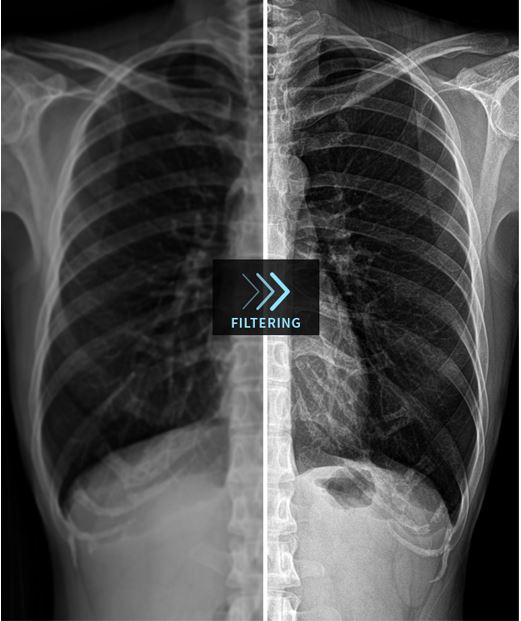

Изучение дозы излучения при рентгеновских исследованиях: визуализация